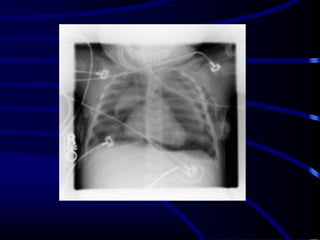

A 27-year-old man is referred to you for evaluation of an

abnormal chest radiograph. About 5 months ago, he consulted

a doctor because of excessive thirst. Evaluation resulted in the

diagnosis of diabetes insipidus, which responded favorably to

desmopressin administered nasally. Recently, he started to

notice shortness of breath when climbing stairs, and a chest

radiograph was obtained.

•Patient history reveals significant tobacco smoking, up to two

packs daily, for at least 14 years. The patient noticed the

shortness of breath for at least 2 years, and recently, he noted

a point of tenderness over the chest wall, lateral to the

posterior axillary line on the left.

•Oxygen saturation is 94% while breathing room air, and the

rest of his vital signs were normal. Auscultation reveals only

rare crackles without prolongation of the expiratory phase.

There is a point of tenderness over the left sixth and seventh

ribs in the posterior axillary line, and a chest CT scan is

obtained.